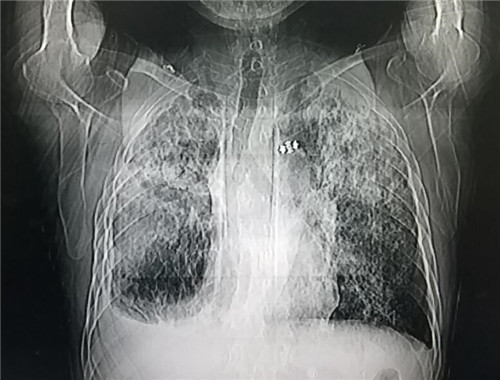

聽取主治醫(yī)生匯報(bào)過程中,李慶華主任單刀直入的指出患者肺部疑似塵肺,要求醫(yī)生再次詢問患者工作履歷,綜合患者煤礦、磚廠、化肥廠工作經(jīng)歷以及相關(guān)指標(biāo),李慶華主任考慮是塵肺導(dǎo)致雙肺纖維化合并重癥肺炎,對現(xiàn)有抗生素使用方案給予指導(dǎo)后,強(qiáng)調(diào)心衰注意事項(xiàng),有的放矢的糾正血氧、預(yù)防肝腎衰竭。